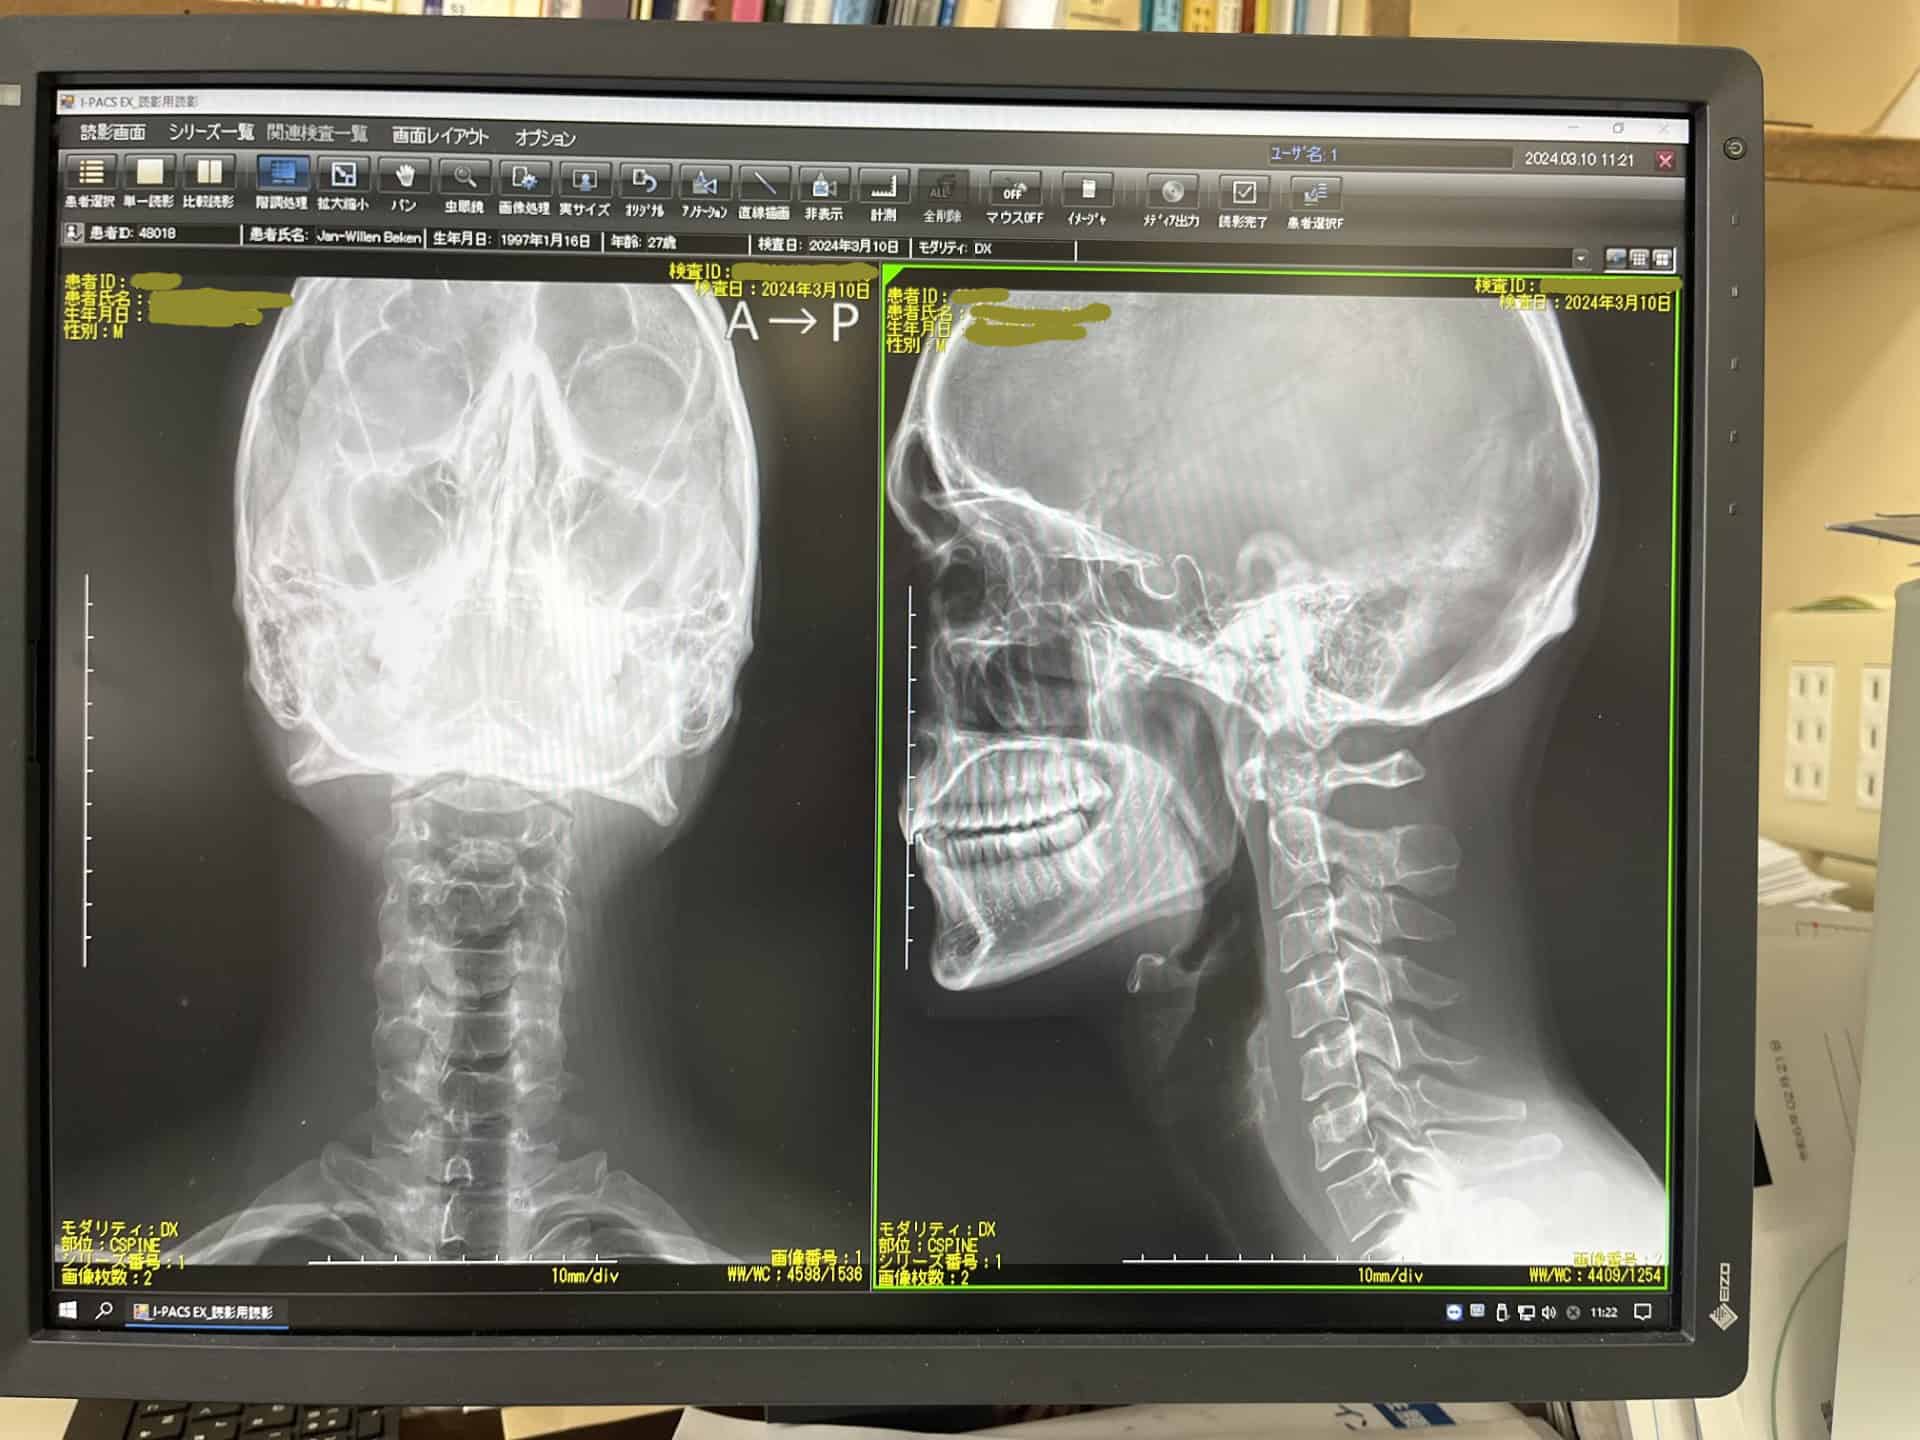

My face was bleeding, my helmet was cracked, but what scared me most was my neck. It didn’t just hurt it felt wrong. Something had shifted. I felt tingling down my body, and for a moment, I wondered if I was paralyzed. But I stood up. I skied down. I told myself I was okay. We got back on the lift and that’s when everything went black.

X-rays showed no breaks. They gave me painkillers and sent me home.